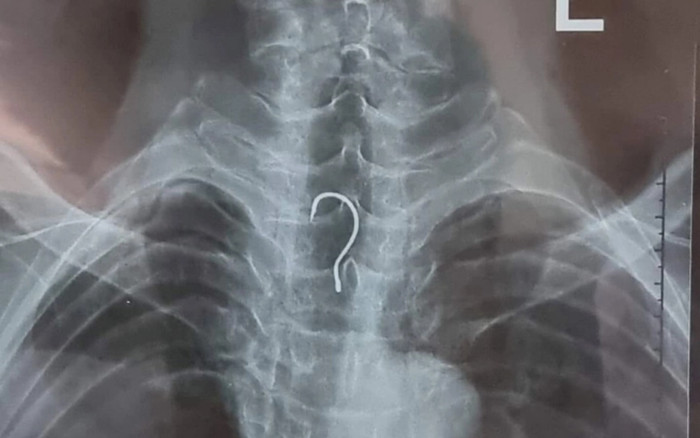

Ảnh chụp X-quang cho thấy dị vật nằm trong cơ thể bệnh nhân. (Ảnh: BVCC).

Sau khi được đưa vào bệnh viện, bệnh nhân đã được tiến hành chụp phim x-quang và nội soi thực quản - dạ dày - tá tràng.

Khi tiến hành nội soi, các bác sĩ phát hiện dị vật nằm ở trong thực quản của bệnh nhân, kíp nội soi đã tiến hành gắp dị vật là lưỡi câu có kích thước 4 x 1,5cm. Sau soi gắp, bệnh nhân A. đã ổn định, đang được tiếp tục theo dõi tại viện.